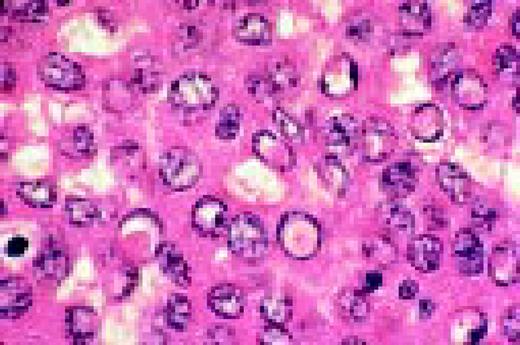

Slide L40

Multiple myeloma, bone marrow aspirate. The marrow has been completely replaced by abnormal plasma cells. A binucleate plasma cell is seen in the center of the field.FIG40